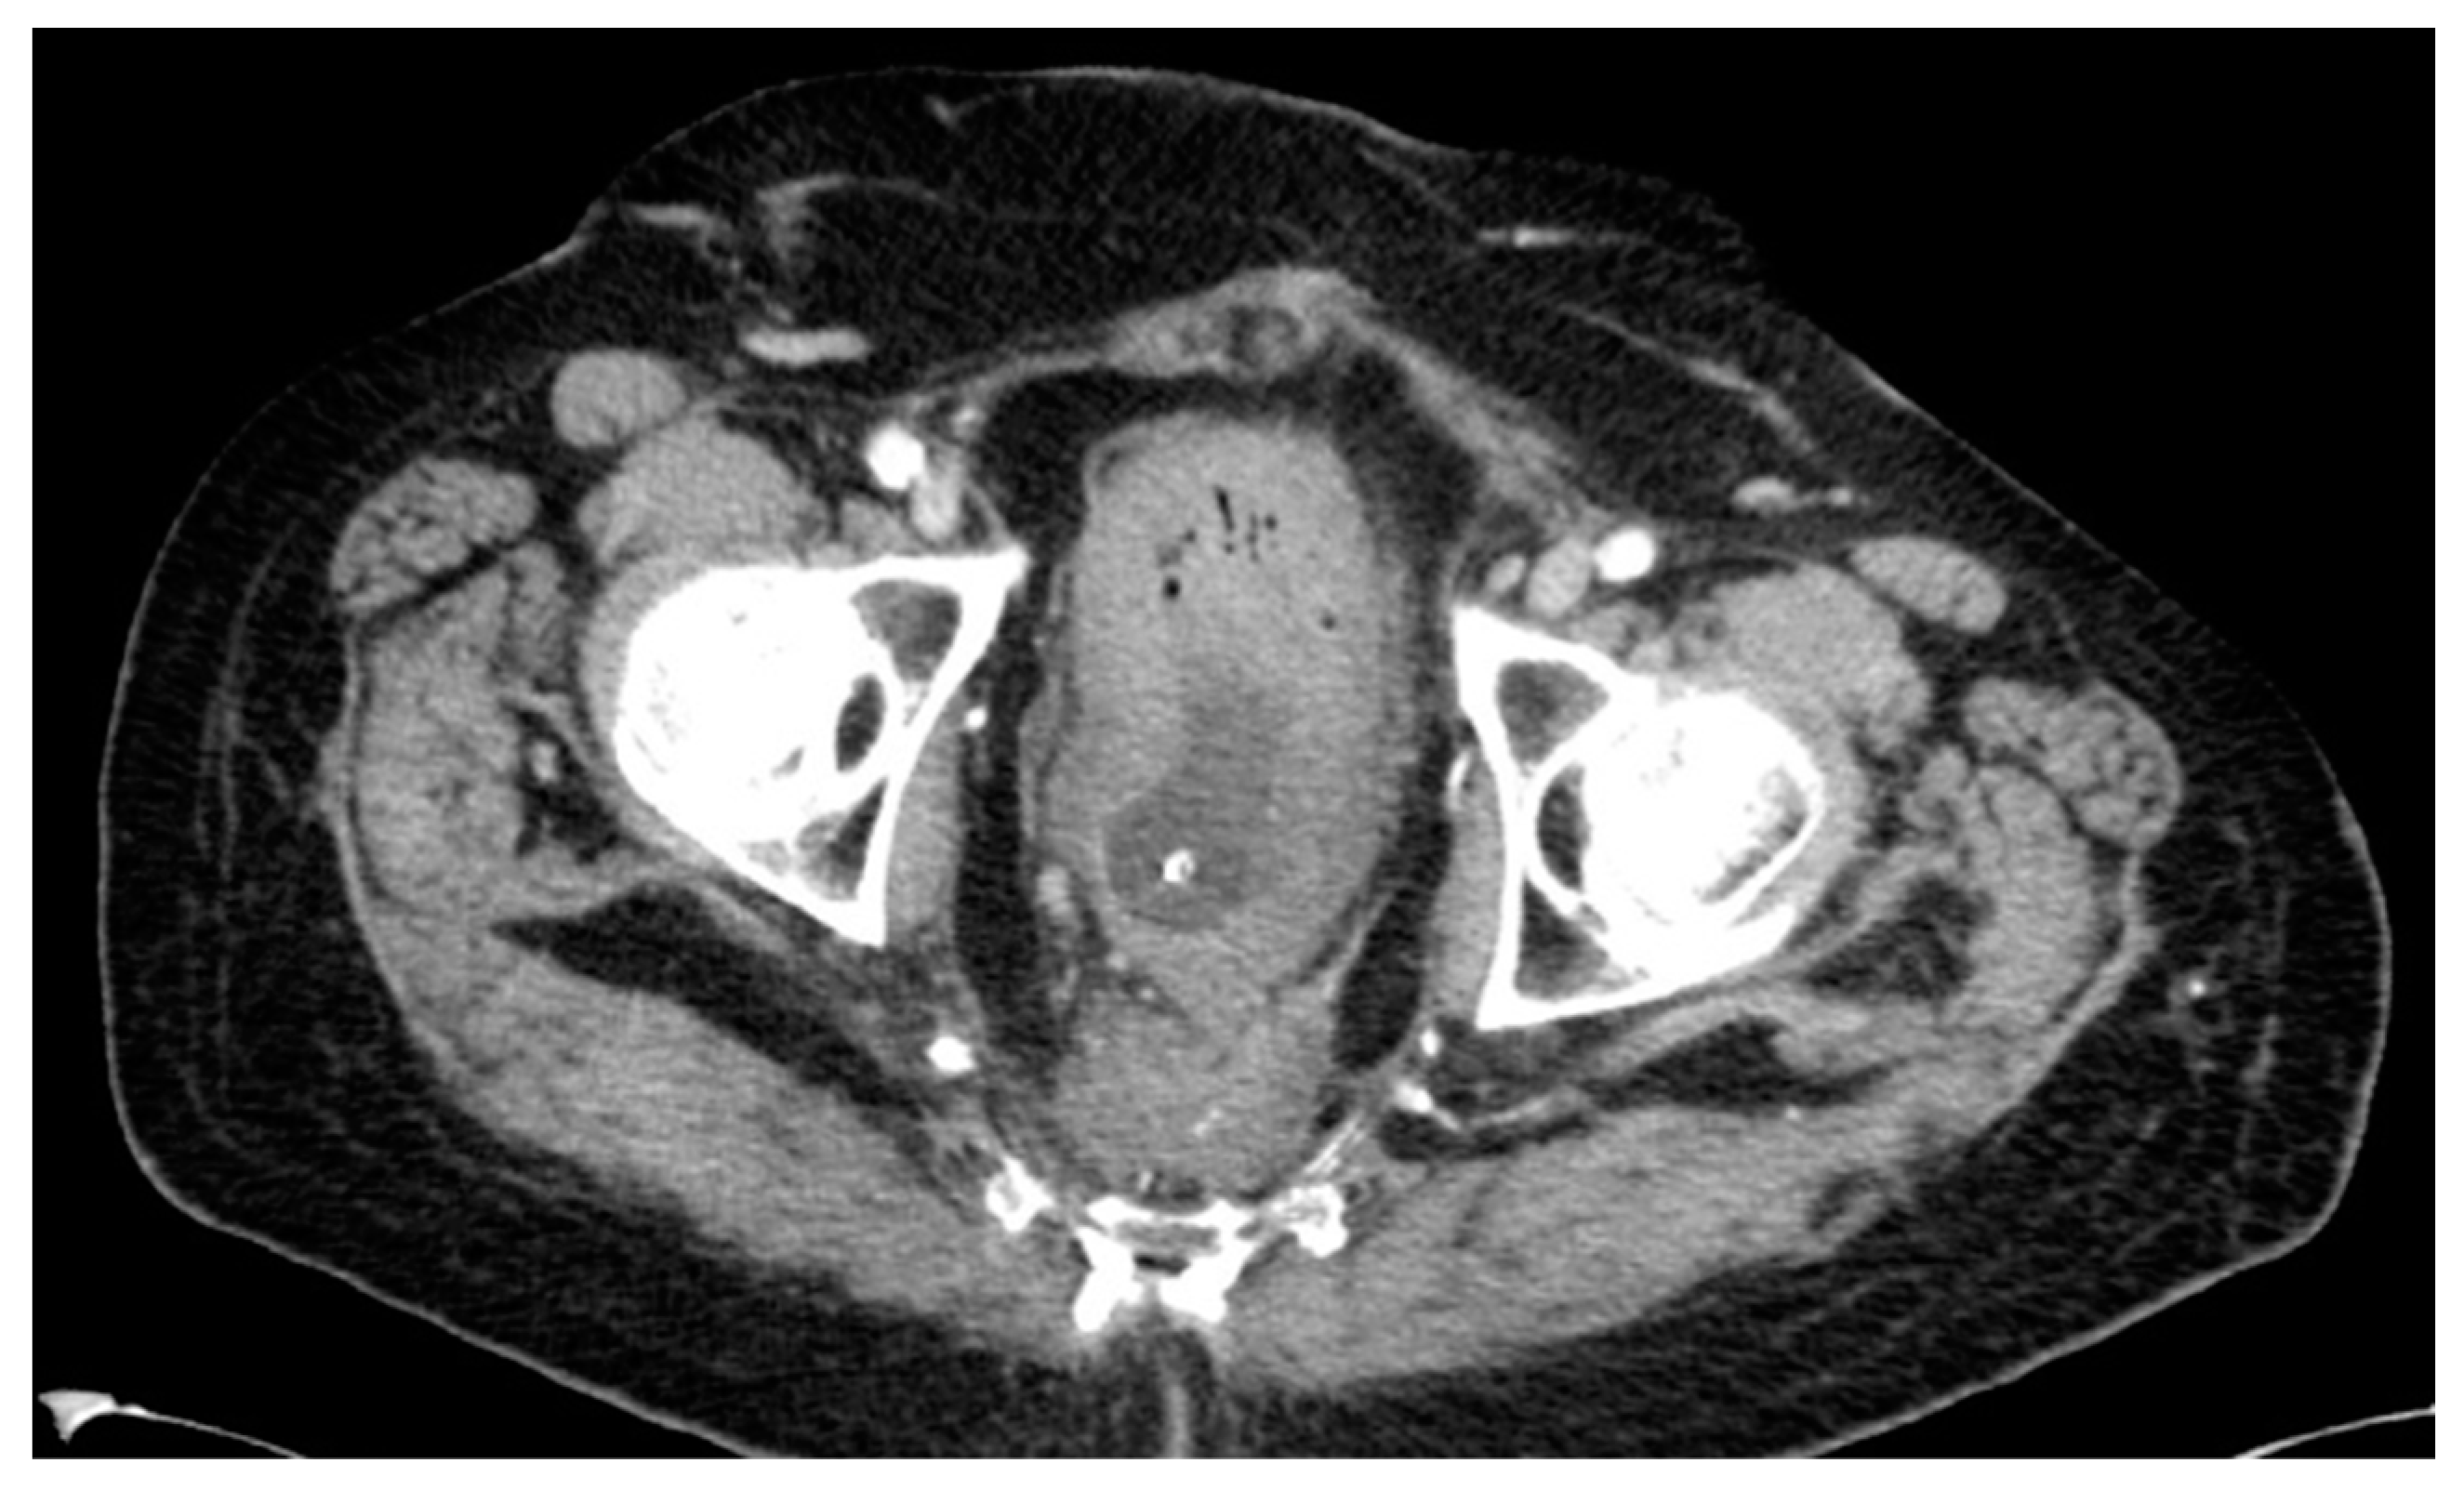

Lastly, one patient developed a presacral mass and received local radiation in combination with chemotherapy, unfortunately without any response. The 68-year-old male initially had a bulky, low-lying T4-tumor with stenosis. He received an end-colostomy prior to RCT and a radical APR afterwards in September 2001. Pathology revealed a node-negative ypT3. The patient refused adjuvant treatment. A CT scan in 2012, which was undertaken because of perineal pain, showed a presacral mass (see Figure 8). CT-guided biopsy confirmed a local recurrence 126 months after APR. The palliative radiation was well tolerated by the patient and was followed by chemotherapy. The patient died in September 2013, 18 months after diagnosis of recurrence.

Figure 8. CT scan #2.